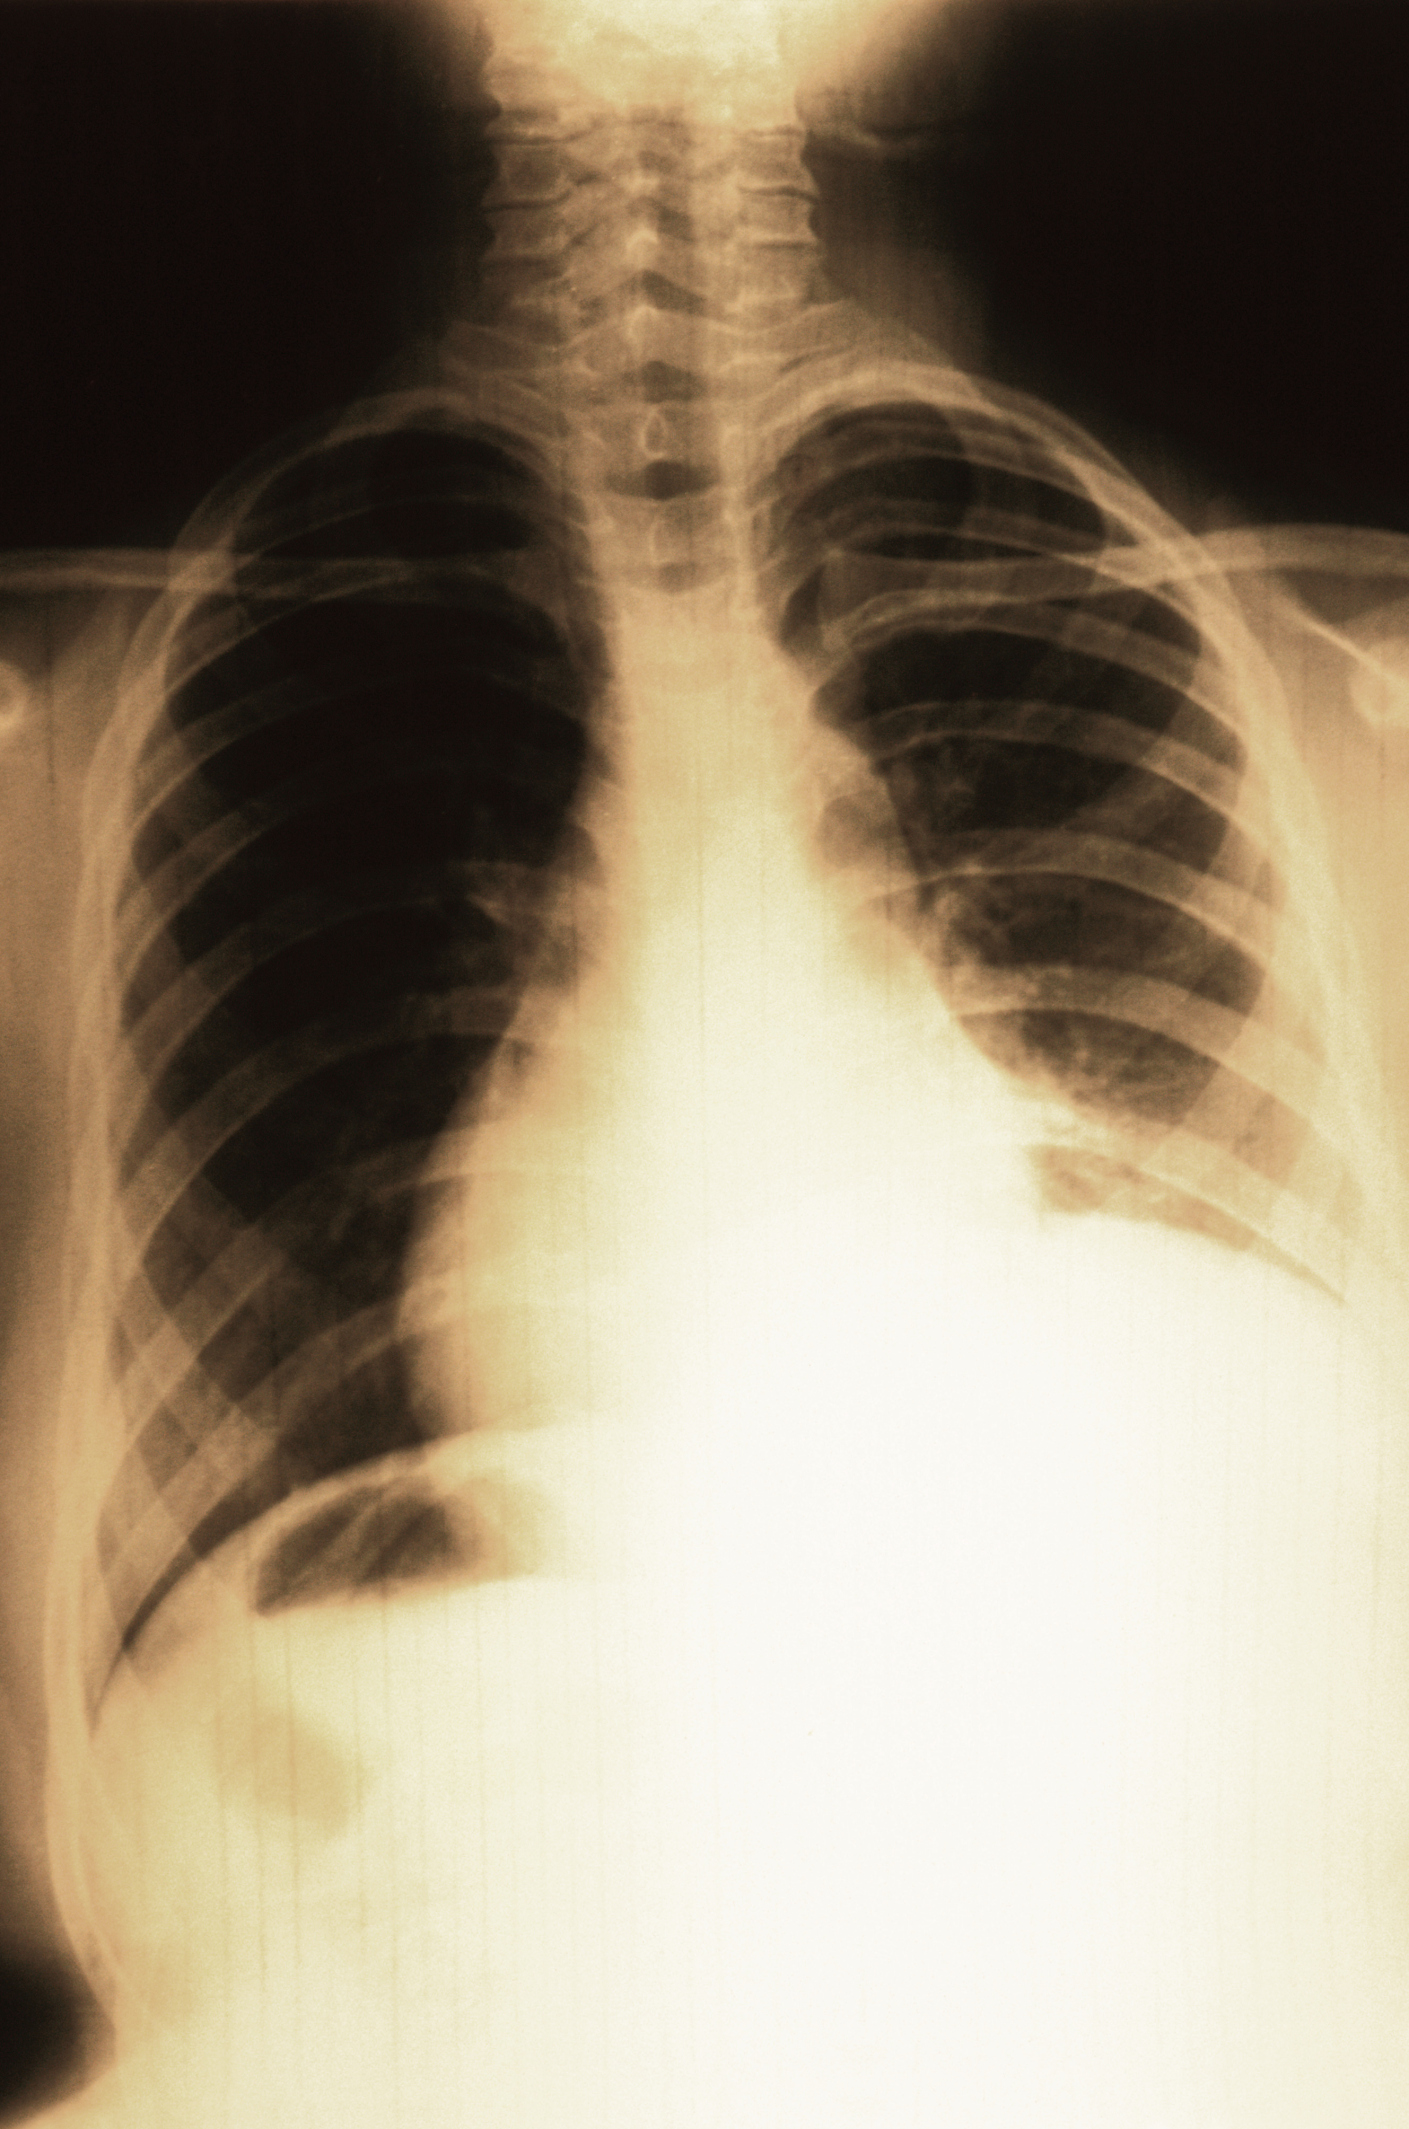

Chest Xray shows Hyperinflated left lung with extreme mediastinal shift